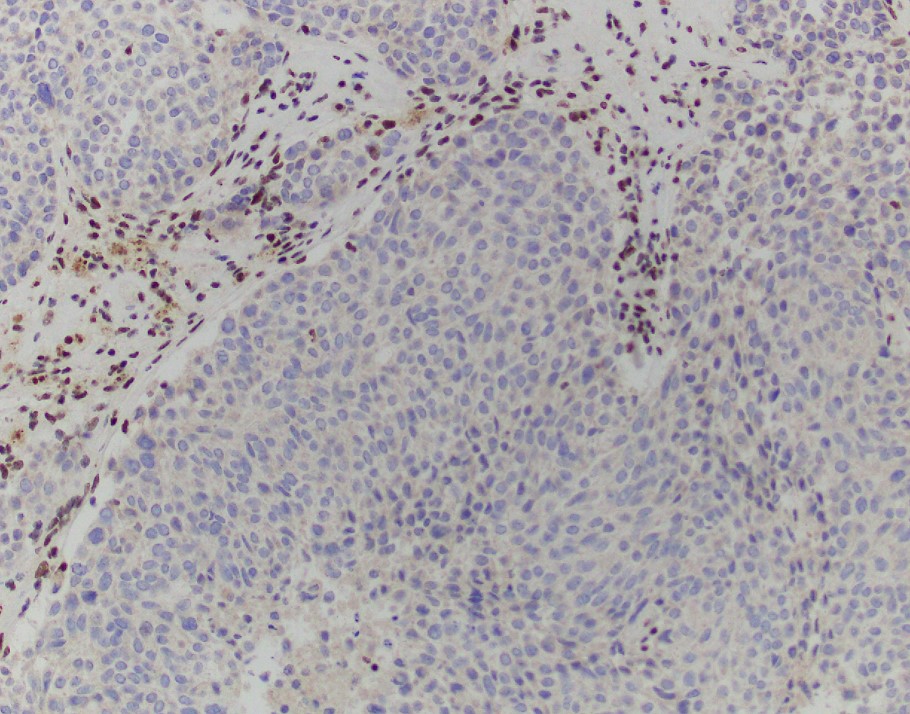

An INI-1 immunostain will show loss in neoplastic cells, confirming the diagnosis of INI-1 (SMARCB1)- deficient sinonasal carcinoma.

Explanation: INI-1 (SMARCB1)-deficient sinonasal carcinoma, currently listed as a subtype of sinonasal undifferentiated carcinoma (SNUC) in the current WHO Classification of Head and Neck Tumors, is a poorly differentiated sinonasal carcinoma defined by loss of nuclear INI-1 expression due to SMARCB1 deletion (1). Histologically, they have a definitive (adeno)carcinoma appearance unlike other INI-1-deficient tumors such as epithelioid sarcoma and atypical teratoid/rhabdoid tumor. INI-1-deficient sinonasal carcinoma shows islands of eosinophilic/oncocytoid and plasmacytoid carcinoma cells with variable glandular differentiation to include focal intracellular/intraluminal mucin production, and may also show a basaloid appearance (2). INI-1 (SMARCB1)-deficient sinonasal carcinoma typically shows expression of CK7. In one report 3 of 10 showed p40 expression, 4 of 12 examples showed CDX2 expression, and 3 of 12 showed CK20 expression (3). Variable/weak expression of neuroendocrine markers has been described. INI-1 (SMARCB1)-deficient sinonasal carcinoma is negative for high-risk HPV and EBV and is negative for S100 protein expression.